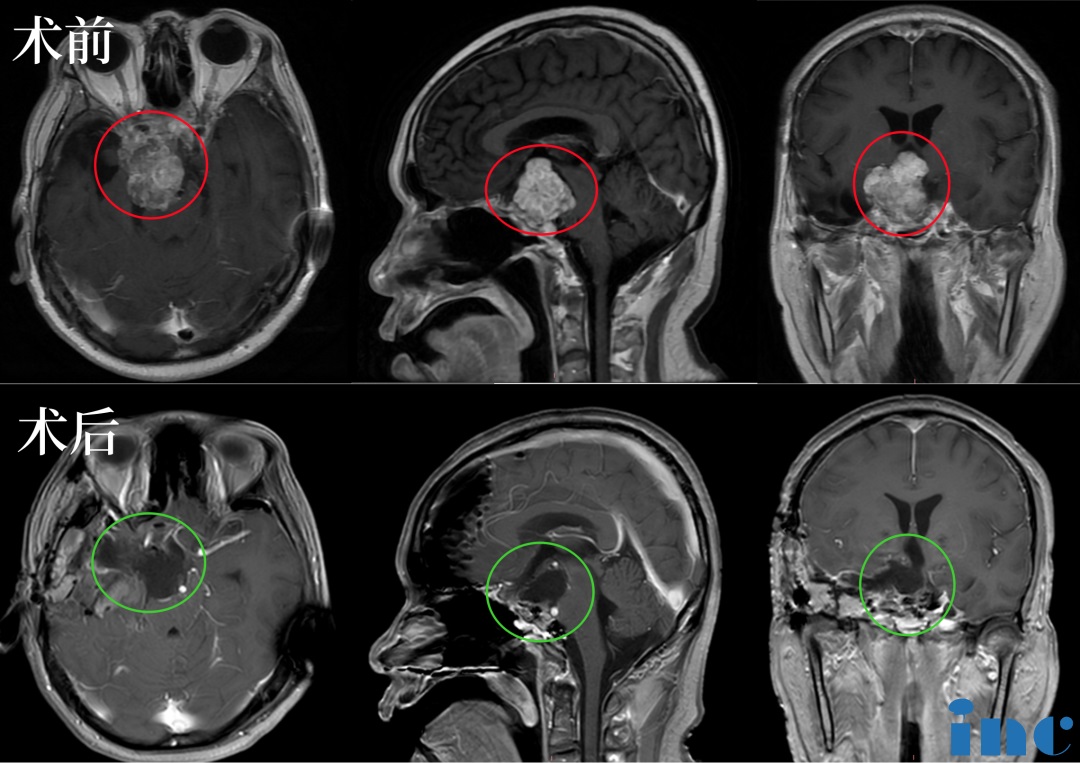

术前:肿瘤体大,广泛累及颅底结构,侵蚀斜坡、鞍内鞍上、海绵窦区,包裹右侧颈内动脉。肿瘤向上推挤视神经、视交叉,到达三脑室底部;向后上方推挤脑干和基底动脉,部分肿瘤边缘与脑干分界欠清。

2023年5月,福教授应邀访问苏州大学附属独墅湖医院(苏州市独墅湖医院),苏先生抓住了这个机会,咨询福教授能否为自己手术,在经过一系列评估以及术前紧急补充激素等措施,2023年5月15日,INC法国福教授为苏先生做了四次开颅手术,在术中,福教授联合应用显微镜和内镜,运用的“筷子手法”,术后当晚核磁显示肿瘤已基本全切。这对夫妻是幸运的,在这场风险较大、具挑战的手术中重获新生。

术后苏先生神志清楚,四肢活动良好,无新增并发症。苏先生妻子无比感谢福教授,虽然不会英文,但是她还是通过翻译软件给福教授亲手写了一封英文感谢信以示感激之情。